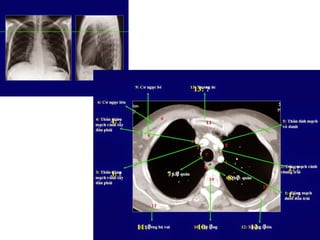

2/XEM HÌNH “SCOUT VIEW” ĐỂ BiẾT VỊ TRÍ LÁT CẮT

PA SCOUT X-RAY

October 31, 2014 6

2/XEM HÌNH “SCOUTVIEW” ĐỂ BiẾT VỊ TRÍ LÁT CẮT PA SCOUT X-RAY October 31, 2014 6